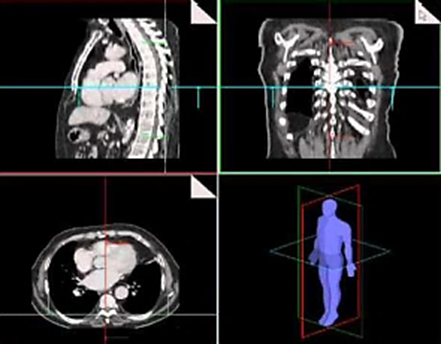

Just like X-ray devices, tomography uses the method of transmitting energy to obtain a 2-D image from any plane in the body. The image of 2-D slices obtained by tomography is called a sinogram. In Computed Tomography, these sinogram images are combined to create images with more 3-D anatomical details.

X-rays and the detector revolve around the patient while creating a 3-D image in Computed Tomography.

Computed Tomography shows the shape and placement of organs, soft tissues, and bones quite clearly. In addition, CT examinations help doctors in the diagnosis of a simple cyst (formation in the form of a sac with a liquid or semi-liquid substance inside) and a solid tumor (tissue mass formed) to better evaluate the diseases provides. More importantly, CT provides much more detailed images than direct radiography, helping to better visualize the internal structure of organs in assessing the spread of cancers. However, it can cause some problems caused by ionized radiation as an X-ray beam is used.